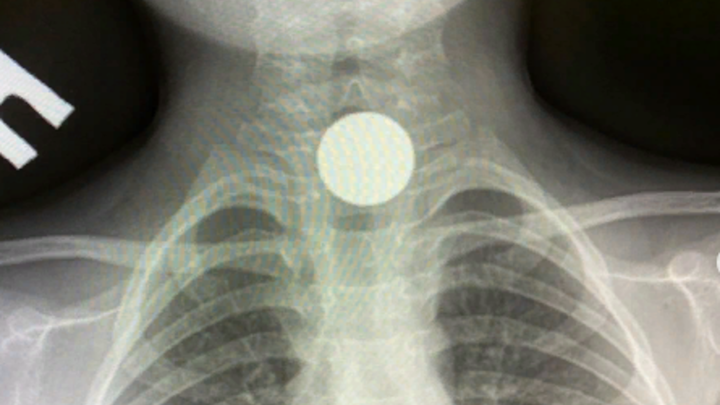

В Туапсе врачи достали монету из пищевода 4-летнего мальчика

Накануне в приёмный покой районной больницы Туапсе поступил 4-летний мальчик с инородным телом в ЖКТ. Его незамедлительно направили на обследование.

Как рассказал в Instagram доктор Саакян, была проведена рентгенография. В пищеводе у ребёнка обнаружили монету. Врачи незамедлительно провели лечебную гастроскопию под эндотрахеальным наркозом.

Монету из пищевода ребёнка удалось достать без оперативного вмешательства. В данный момент здоровью мальчика ничего не угрожает.